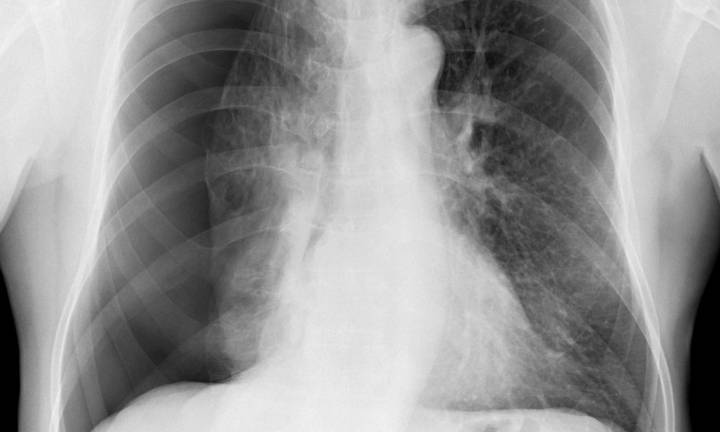

China: Researchers have found in a new study that pleural abrasion offers better perioperative outcomes , making it ideal for patients seeking rapid recovery or those with limited surgical tolerance. In contrast, parietal pleurectomy, though associated with a heavier perioperative burden and higher risk of postoperative hemorrhage , effectively lowers recurrence rates in patients with recurrent or complex pneumothorax. Postoperative complication rates are similar for both techniques. The study, published in BMC Surgery by Kai Yang and colleagues from the First Clinical Medical School, Gansu University of Chinese Medicine, Lanzhou, aimed to compare the perioperative efficacy and safety profiles of parietal pleurectomy and pleural abrasion when combined with bullectomy for treati